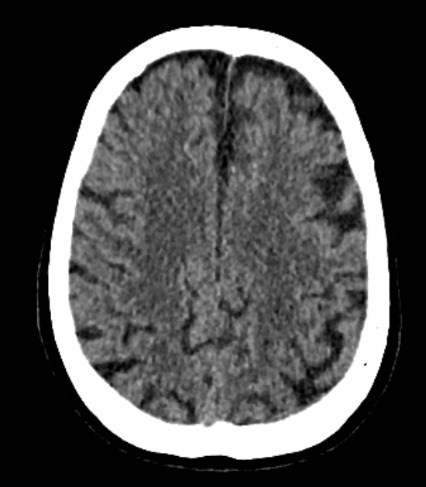

Four months after surgery, she presented to the emergency department due to the onset of motor skill disturbances, prompting evaluation by the neurology department. A cranial CT scan suggested the possibility of a subacute ischemic stroke affecting multiple territories (Figure 1). Further investigation revealed that the patient had visited her primary care physician two months before admission, reporting food intolerance, anorexia and weight loss.